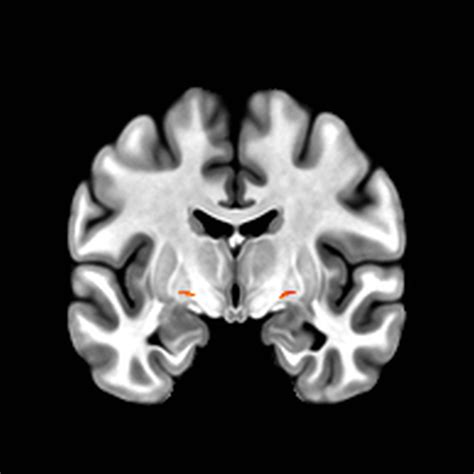

Brain anatomy representation

The Nucleus Basalis of Meynert is located in the substantia innominata, situated in the basal forebrain. While it may appear as a small, unassuming collection of cells, its impact is expansive. It is part of the cholinergic system, which regulates the “background hum” of brain activity. When this nucleus functions optimally, we experience alertness, clear perception, and the ability to focus on tasks despite surrounding distractions.